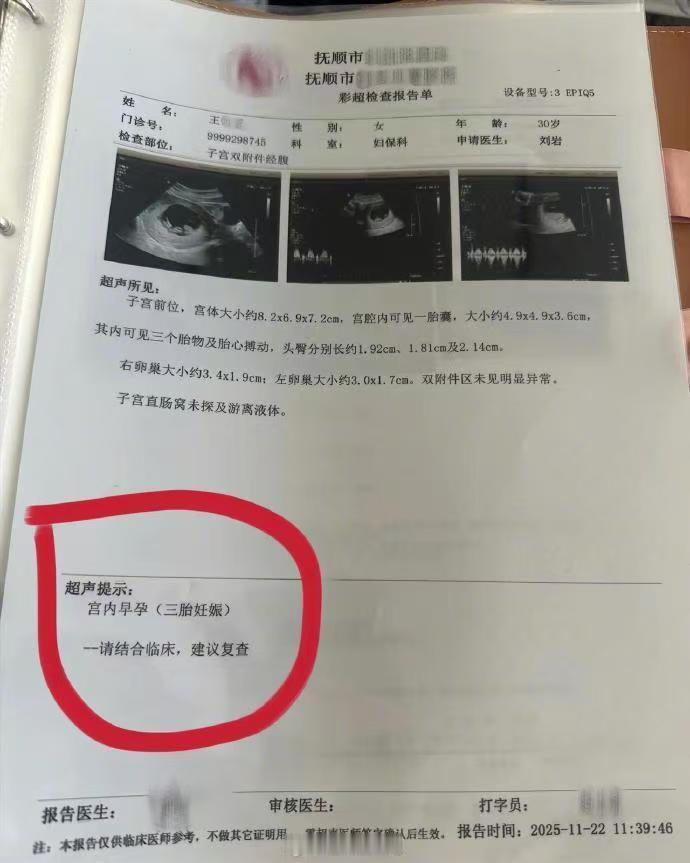

辽宁抚顺的一位准妈妈最近经历了人生中过山车般的时刻。怀孕16周的王女士,原本只是按部就班地进行产检,却在医院拿到了一份极其罕见的诊断报告。从去年11月到12月,短短一个月的时间里,她在医院进行了四次产检,每一次彩超单上的图像都在发生变化——最终确认,她怀上了四胞胎。 这并非普通的四胞胎。根据相关医生的诊断,王女士怀上的是同卵四胞胎。在医学领域,同卵四胞胎的发生率极低,属于非常罕见的个案。更复杂的情况在于,医生指出第四个胎儿为“无心畸胎”。这是一个专业性很强的术语,意味着这个胎儿虽然没有正常的心脏发育,但依然依赖其他胎儿的血液循环在母体内生存。这种特殊的医学状况,无疑给整个孕期增添了巨大的不确定性和风险。 对于普通家庭而言,多胞胎往往意味着双倍的喜悦,但在医学视角下,这更多代表着高风险妊娠。从数据来看,自然受孕情况下同卵四胞胎本就凤毛麟角,而伴随无心畸胎的情况更是让保胎之路布满荆棘。王女士在抚顺当地医院进行的这四次检查,实际上是一个不断排查和确认的过程。每一次彩超,不仅是在数胎儿的数量,更是在评估母体和每一个胎儿的生存质量。 网友们对此议论纷纷,有人感叹生命的奇妙与不易,也有人为即将到来的抚养压力感到担忧。毕竟,四个孩子的降生,对家庭的经济状况、父母的精力都是极大的考验。目前摆在王女士和家人面前的,不仅是喜悦,还有如何根据医生的专业建议,制定最科学、最安全的后续妊娠方案。 这起事件也给广大备孕及孕期女性提了个醒:规范的产检流程至关重要。像王女士这样,通过连续、定期的超声检查,才能及时发现多胎妊娠及胎儿发育异常等特殊情况。面对罕见病例,医学干预和监测是保障母婴安全的最有效手段。祝愿这位准妈妈能平安度过接下来的孕期,也希望这个小生命群体能在现代医学的保驾护航下,迎来最好的结局。 以上内容仅供参考和借鉴